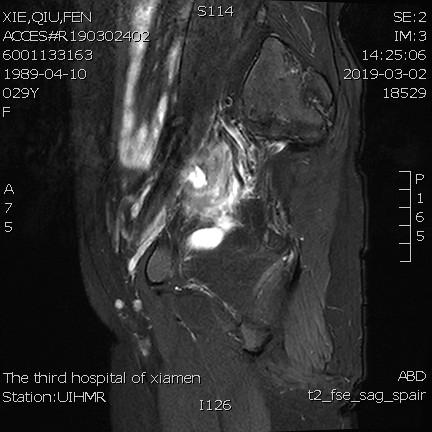

例1

青年女性患者,痛经近10年,近5年痛经明显加重。确诊为子宫腺肌症(弥漫型),经放置曼月乐、注射亮丙瑞林等妇科保守治疗,症状缓解不理想,痛经进行性加重,严重困扰工作与生活。

- 术前MRI显示子宫明显增大,病灶主要位于子宫前壁。

- 术后3个月复查MRI显示子宫明显缩小,前壁病灶萎缩坏死。